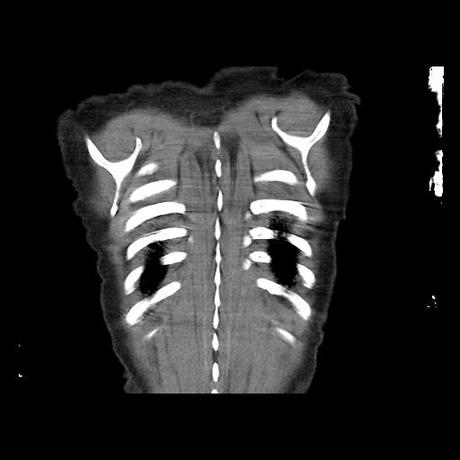

Se realiza volumen de tórax en fase simple, desde los opérculos torácicos hasta los hemidiafragmas, observándose:

Estructuras óseas sin evidencia de lesiones líticas, blásticas ni trazos de fractura. A nivel de cuerpo vertebral de T10 se observa nódulo de Schmorl que distorsiona el borde superior del cuerpo vertebral.

El parénquima pulmonar con areas parcheadas difusas en vidrio despulido combinadas con otras areas hipodensas de baja atenuación debidas a atrapamiento aéreo y engrosamiento intersticial y zonas de fibrosis de predominio en lóbulos medios e inferiores de ambos pulmones.

- LOS HALLAZGOS PUEDEN ESTAR EN RELACIÓN A NEUMOPATIA INTERSTICIAL PROBABLE ETIOLOGIA HIPERSENSITIVA VS AUTOINMUNE/BACTERIANA/FUNGICA.